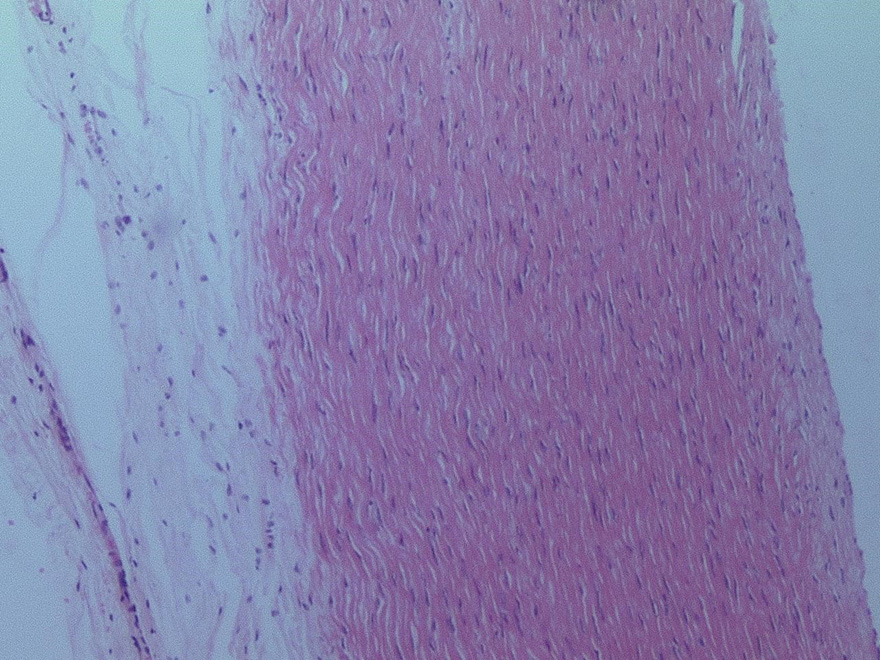

◄ 1.3 Staining techniques